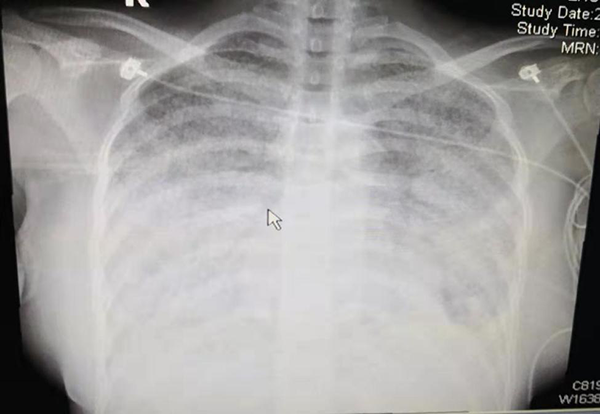

7月10日,周女士這位年輕的母親,順利產(chǎn)下一名寶寶,本以為一家三口開(kāi)始全新的幸福溫馨的生活。但天有不測(cè)風(fēng)云,噩耗突然降臨到這個(gè)原本幸福的三口之家。周女士持續(xù)高燒,并逐漸出現(xiàn)呼吸困難的癥狀。家人十分害怕,立刻送到徐醫(yī)附院東院就診。但周女士入院后仍持續(xù)發(fā)熱,呼吸困難進(jìn)一步加重,出現(xiàn)嚴(yán)重低氧血癥,行氣管插管、呼吸機(jī)支持治療。雖然呼吸機(jī)的參數(shù)已經(jīng)調(diào)至最高水平,吸入純氧,但仍然持續(xù)出現(xiàn)危及生命的低氧血癥。X線提示“大白肺”,診斷為“重癥肺炎重度ARDS”,這是病死率極高的急危重癥。東院ICU緊急聯(lián)系葉英主任會(huì)診,葉英在接到電話后,立刻意識(shí)到這是一場(chǎng)搶救生命的硬仗,立即啟動(dòng)體外生命支持ECMO團(tuán)隊(duì),團(tuán)隊(duì)人員迅速到位,僅30分鐘內(nèi)一切準(zhǔn)備就緒,一場(chǎng)與死神“搶跑”的生死救援開(kāi)始了。